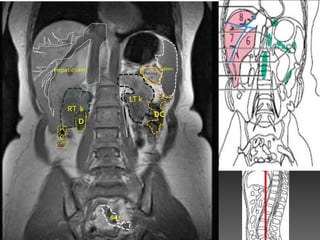

Hepatic vein                            Spleen

Pancrea

LT k

RT k

DC

Sig C

Lk

Rk

RECTUM